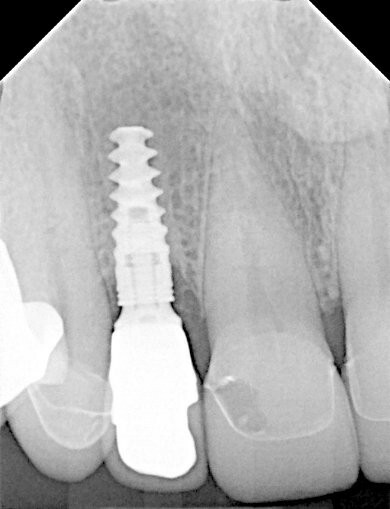

Wir behandelten in unserer Praxis einen Patienten, der über Schmerzen klagte, die durch eine Abszessbildung in Implantatregion 12 verursacht wurden. Das Implantat war ein Jahr zuvor von seinem Allgemeinzahnarzt inseriert worden.

Klinisch und radiologisch zeigte sich eine Entzündung mit Schwellung des Weichgewebes und Pusabsonderung auf Druck. Die Taschentiefe betrug 5-6 mm, der periimplantäre Knochenverlust betrug 3 mm.

Es wurde eine Periimplantitis diagnostiziert und eine Behandlung empfohlen.